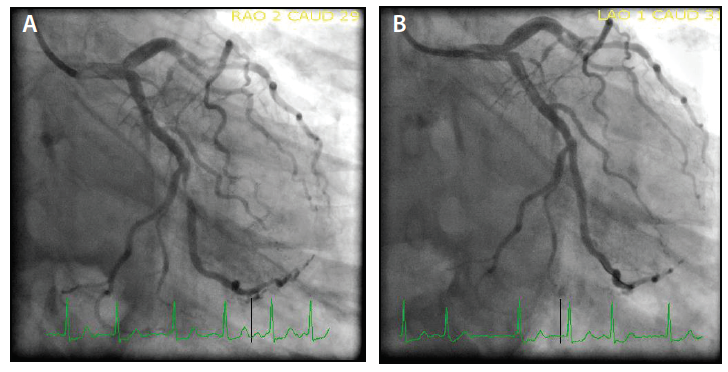

An extra backup (EBU) 3.5 Launcher® guide catheter (Medtronic) was preloaded with the 0.035-inch Railway™ dilator (Figure 5A) to match the 100-cm marker. The JR 4 guide catheter was pulled back over a 0.035-inch J wire secured in the ascending aorta. The assembly of the Railway™ dilator and EBU guide catheter was inserted (Figure 5B) up the right brachiocephalic artery. The dilator was removed, and using a 0.035-inch wire and standard practices, the left main artery was cannulated. The first obtuse marginal artery 90% stenosis (Figure 6A) was successfully treated with the same 1.5-mm balloon and a 2.75- X 15-mm Cobra PzF™ stent, with a very good angiographic result (Figure 6B). Subsequently, the left anterior descending (LAD) lesion (Figure 7A) was successfully treated using a 3.5- X 15-mm Cobra PzF™ stent, which was postdilated with a 4-mm noncompliant balloon showing a very good angiographic result (Figure 7B). After completing final orthogonal angiography, the guide catheter was removed over a 0.035-inch wire to the right RA and a TRAcelet™ compression device (Medtronic) (Figure 8A) was applied.